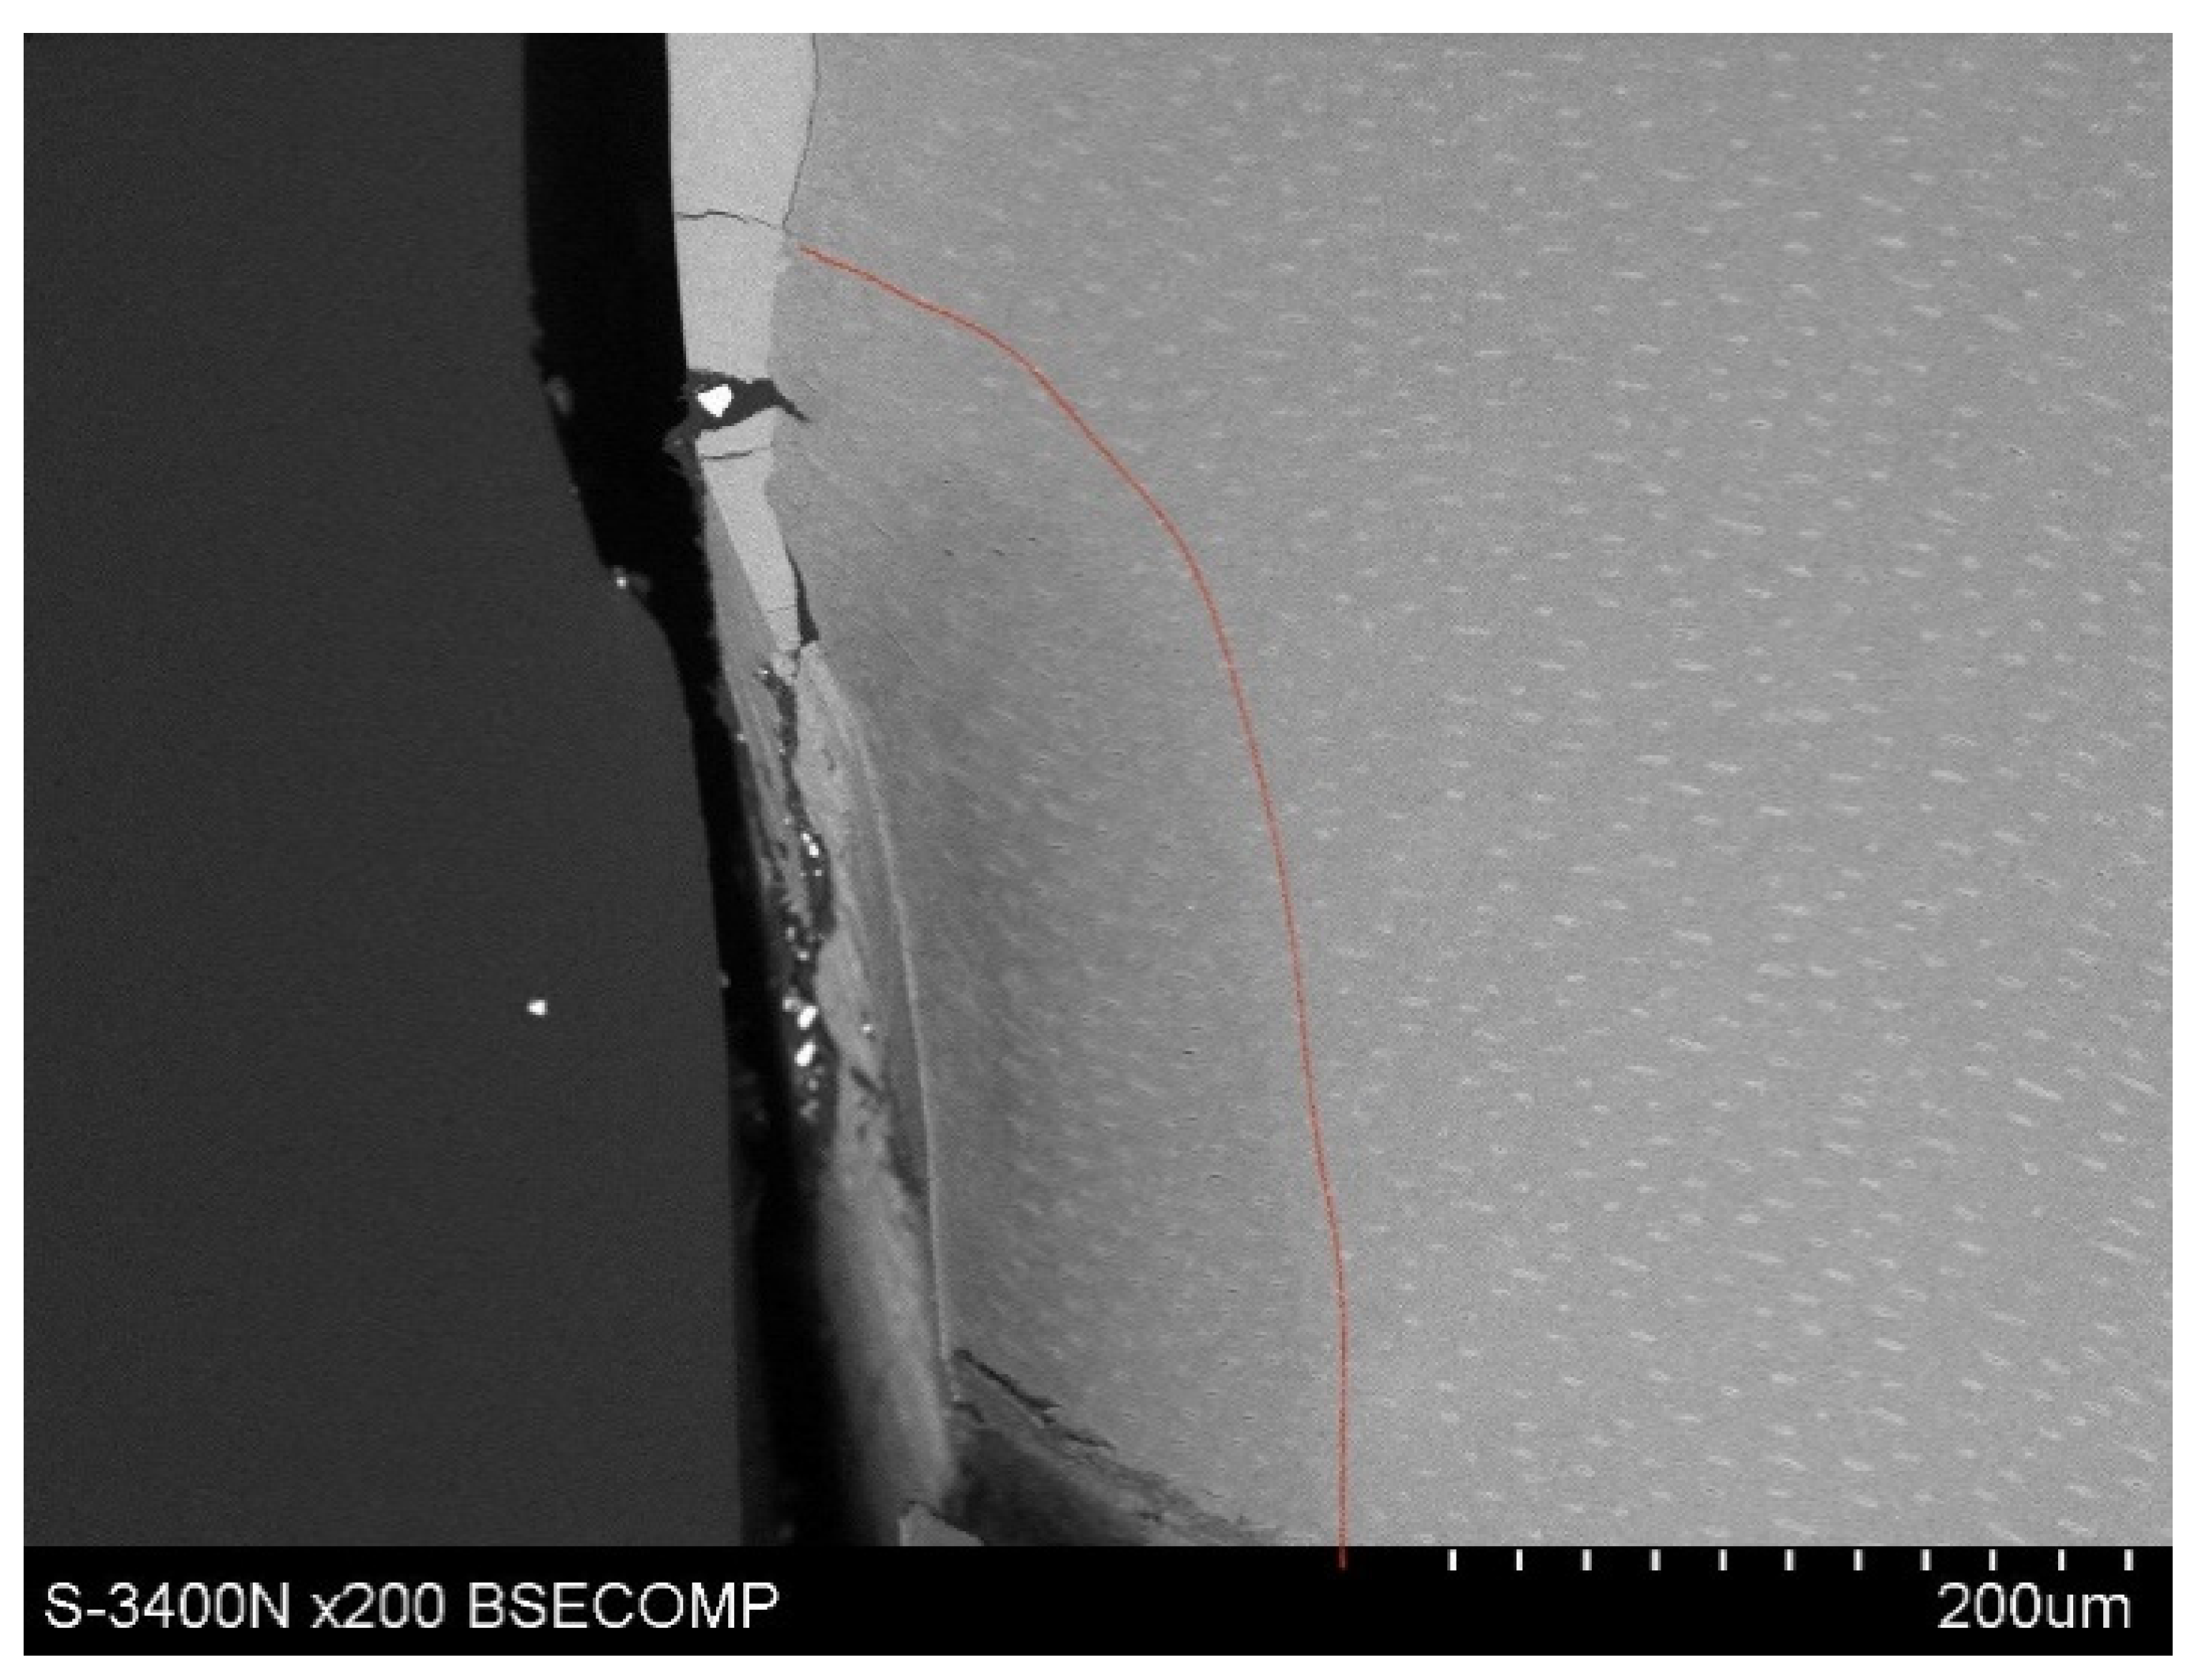

The examined area was root cementum, 4–6 mm below the tooth neck (Figure 4).

The study also showed that yttrium fluoride may have insufficient adhesion to the outer surface of tooth root cementum. Longitudinal sections of the teeth made after embedding them in resin showed large amounts of yttrium fluoride particles in the resin used to inlay specimens, sporadically on the surface of root cementum and deep into the cementum and dentin tissue of the root (Figure 5). This demonstrates high affinity of the yttrium fluoride preparation to the used resin (after completion of the crosslinking process, the resin shrinks slightly, forming a gap between the surface of root cementum and resin—Figure 6).

Observations of cementum and root dentin tissue infiltration—resin tissue infiltration is visible to a depth of about 80–120 μm without the use of a tracer, which due to agglomeration and particle size remained on the cementum surface or in the resin used for inlaying (Figure 7, Figure 8, Figure 9, Figure 10 and Figure 11).

Figure 4. Tooth longitudinal section with highlighted area of SEM observations.

Figure 5. Icon + YF3 specimen sample: image of the longitudinal section of root cementum: YF3 particles in the mounting resin.

Figure 7. Polished section from the study group, Icon + 2% YF3, visible gradual brightening of the infiltrated root dentin, depth of infiltration at approx. 130 μm.